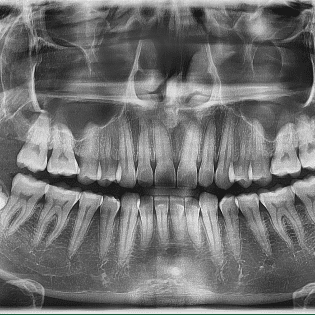

Bước 2: Chụp X quang, đánh giá răng và tổn thương( nếu có)